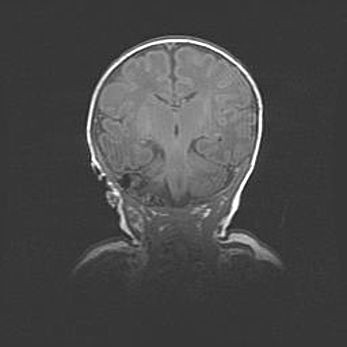

Открытая гидроцефалия.

Возраст: 6 месяцев 15 дней

Вес: 6200 г

Пол: женский

Окружность головы: 41 см

Срок гестации: 38 недель

Гидроцефалия головного мозга у новорожденных – это скопление избыточного количества цереброспинальной жидкости в головном мозге. Ее избыточное скопление в мозге приводит к патологическому расширению желудочков мозга (четырех полостей, расположенных в глубине белого вещества мозга, заполненных цереброспинальной жидкостью и связанных узкими проходами).

Открытый тип гидроцефалии (сообщающаяся) наблюдается тогда, когда нарушен механизм всасывания ликвора в системный кровоток. При этом типе причиной заболевания чаще всего является перенесенные ранее инфекции (например: менингит),  либо же наличие крови в субарахноидальном пространстве.